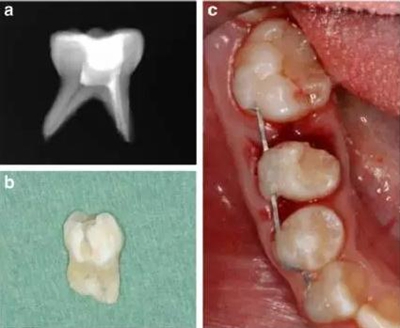

牙槽固連技術(shù)包括在局麻下拔除乳磨牙,然后進行近中根的體外根管治療,對牙冠做復(fù)合樹脂的修復(fù),進行2mm的根尖切除術(shù)和偏側(cè)牙根切除。為了達成牙槽固連,我們采用了根尖孔閉合且在口外干燥60分鐘以上脫位牙的處理方法。用刮治器從根面上收集牙周膜細胞。拔除6分鐘后,用鹽溶液沖洗牙槽窩,將近中牙根帶輕微壓力重新植入。為了保持牙齒穩(wěn)定,從右側(cè)尖牙到右側(cè)第一磨牙應(yīng)用0.016’’*0.022’’不銹鋼方絲作為牙弓夾板。